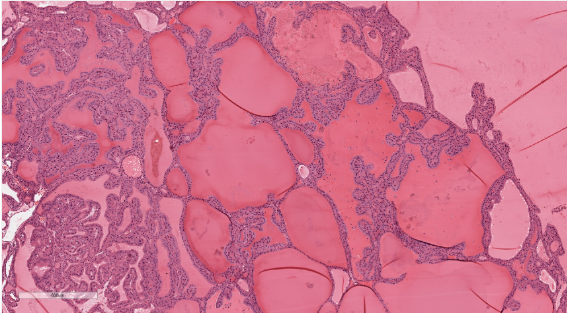

First image: FA with pap architecture. On high power the cells are often columnar. The nuclei are basally located and are small, round, and dark. Nuclear features of papillary thyroid carcinoma are always absent. The edematous fibrovascular cores show embedded follicles.

Below image; Follicular adenoma with papillary architecture - Low power view showing large colloid-filled follicles and complex papillary infoldings of the lining epithelium.